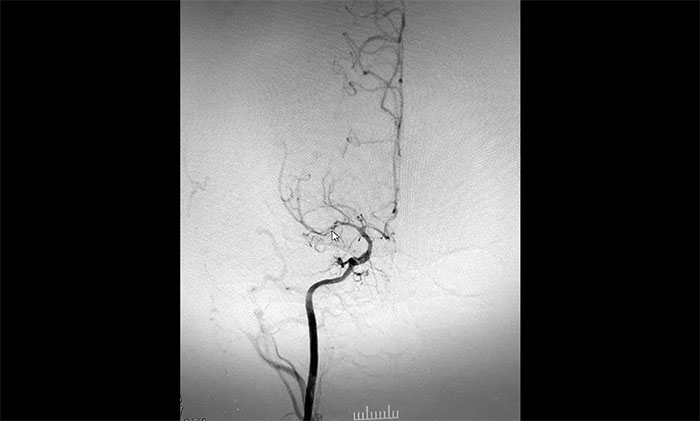

“拨开迷雾” 科学评估 定制方案

入院后,赵先生的DSA(脑血管造影)检查再次明确“烟雾病”表现:双侧大脑中动脉主干管腔纤细、分支细小;周围代偿性小血管网建立;右侧颈内动脉C3-4段纤细,显影毛糙;两侧颈内动脉C4-6段钙化形成伴管腔轻—中度狭窄。

▲DSA异常血管造影图

神经外科团队综合DSA检查结果和患者症状表现,进行了科学、审慎的评估。于耀宇主任谈到,患者双侧颈内动脉虹吸部和大脑中、前动脉主干近段明显狭窄、近乎闭塞,异常血管网形成。双侧大脑半球多发供血区灌注不足,尤以右侧缺血较为明显。